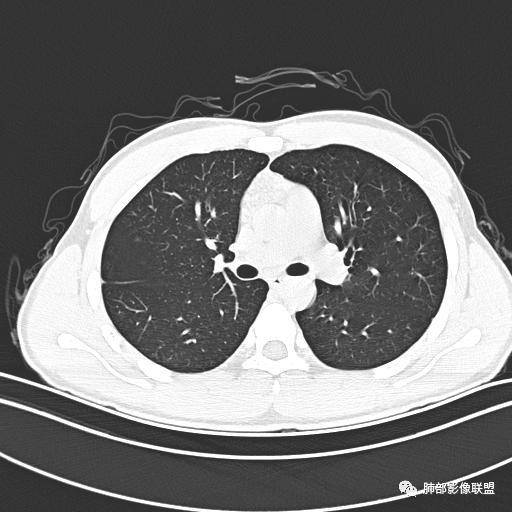

男,19岁

主  诉:发热、全身皮疹2天。

现病史:患者源于2天前受凉后出现发热,最高体温为38.5℃,且颜面部出现少量皮疹,无鼻塞、流涕、咳嗽、咳痰,未在意而未作特殊处理,次日全身皮疹逐渐增多至全身,伴轻度瘙痒,在当地卫生所给予抗病毒、抗感染治疗(具体用药不详)体温有所下降,但皮疹无明显消退,无腹痛、头痛,食欲无明显减退,为进一步诊治,遂于今日急来我院求治,患者目前精神尚可,体力正常,食欲正常,睡眠正常,体重无明显变化,大便正常,排尿正常。

小强:青年,发热,皮疹;双肺散在结节,周围磨玻璃,点晕征,疱疹病毒感染,鉴别荚膜组织胞浆菌,结核。 大雄:青年,急性起病,发热伴全身皮疹2天,抗病毒治疗体温有下降。双肺随机分布大小不等类圆结节,“点晕征”。考虑水痘-疱疹病毒(VZV)血播询问接触史,查体皮疹分布以及形态基本可诊断。 王开金江津中心医院呼吸科:青年男性,起病急,病程短,以发热,皮疹为首发症状,感染指标以单核细胞升高为主,胸部ct双肺多发结界,周围有晕,点晕表现,随机分布,同意於老师意见,水痘疱疹病毒血流感染累及肺。 王秀仙:双肺多发大小不等结节,周围有晕,边缘模糊,呈点晕征表现。青年,急性起病,发热伴全身皮疹2天,抗病毒治疗体温有下降。考虑疱疹病毒。鉴别荚膜组织胞浆菌。 傅昌瑜:19岁男性,发热、全身皮疹2天,单核细胞增高,双肺多发结节,结节边缘见边界不清磨玻璃影。点晕征+发热、全身皮疹+单核细胞增高——考虑水痘-带状疱疹病毒肺炎。 一切∮随缘:年轻男性,发热,皮疹两天,实验室,CRP,PCT增高,影像:双肺多发散在磨玻璃结节,边界欠清,大小不等,呈点晕征改变,以血管束周围分布为主,局部血管束略增粗,其它无明显改变,考虑:1:病毒性肺炎(水痘疱疹病毒?不知道皮肤有无改变)2:真菌(组织胞浆菌,血管侵袭性肺曲霉)3:GPA4:寄生虫(实验室没有看到嗜酸细胞增高) 赵山河:双肺散在结节,周围有晕,边缘模糊,呈点晕征表现。青年,急性起病,发热伴全身皮疹2天,抗病毒治疗体温有下降。考虑水痘—疱疹病毒感染。洪桥爱:青年男性,发热、皮疹2天,伴瘙痒,皮疹于面部首发,之后进展至全身,虽然没有对皮疹进行描述,但是从出疹时间及皮疹进展情况,伴瘙痒,应该就是个水痘患者;CT提示双肺随机分布结节影,部分结节伴有边界不清晕征,考虑水痘血播肺。 刘强:年轻男性,急性起病,皮疹,发热,抗感染治疗体温下降,说明有效。影像表现为散在点晕征,感染类疾病谱(疱疹病毒,真菌,结核),结合年龄,皮肤皮疹,考虑水痘-疱疹病毒性肺炎。 小兜:男性,19岁,发热皮疹两天,颜面部至全身,CRP,降钙素及单核增高。CT示双肺散在小结节,周围伴磨玻璃影,点晕征,考虑为水痘-带状疱疹病毒(varicella-zoster virus,VZV)肺炎 必有路:青年,皮疹+发热+“点晕征”→水痘-疱疹病毒(VZV) 许慧良:青年男性患者,发热、皮疹2天,体温最高38.5℃,第3天皮疹扩展至全身,伴瘙痒,胸部CT:双肺多发随机分布的小结节,结节周边见边界模糊的晕征,考虑水痘病毒感染流心明智:男,19,急性起病,发热伴全身皮疹2天。出疹顺序头→全身,抗病毒有效。胸部CT:两肺多发大小不等类圆形实性小结节影,随机分布,结节周围环绕GGO,边界模糊,呈点晕征。出疹特点是关键,未提示。考虑:血播病毒性肺炎,水痘-疱疹病毒?麻疹?鉴别荚膜组织胞浆菌、TB、血管炎、寄生虫等。 浪迹天涯:病灶多为5-10mm大小结节,结节周围可见磨玻璃样的晕环,常多发,可分布于肺内任何区域,考虑水痘—带状疱疹病肺炎如果短时间内有新的一个区域浸润,更加能说明,